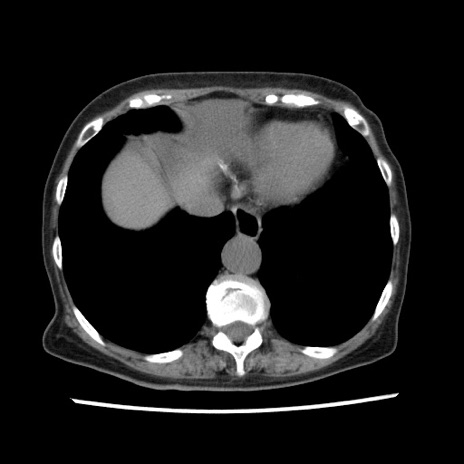

冠状断像

矢状断像